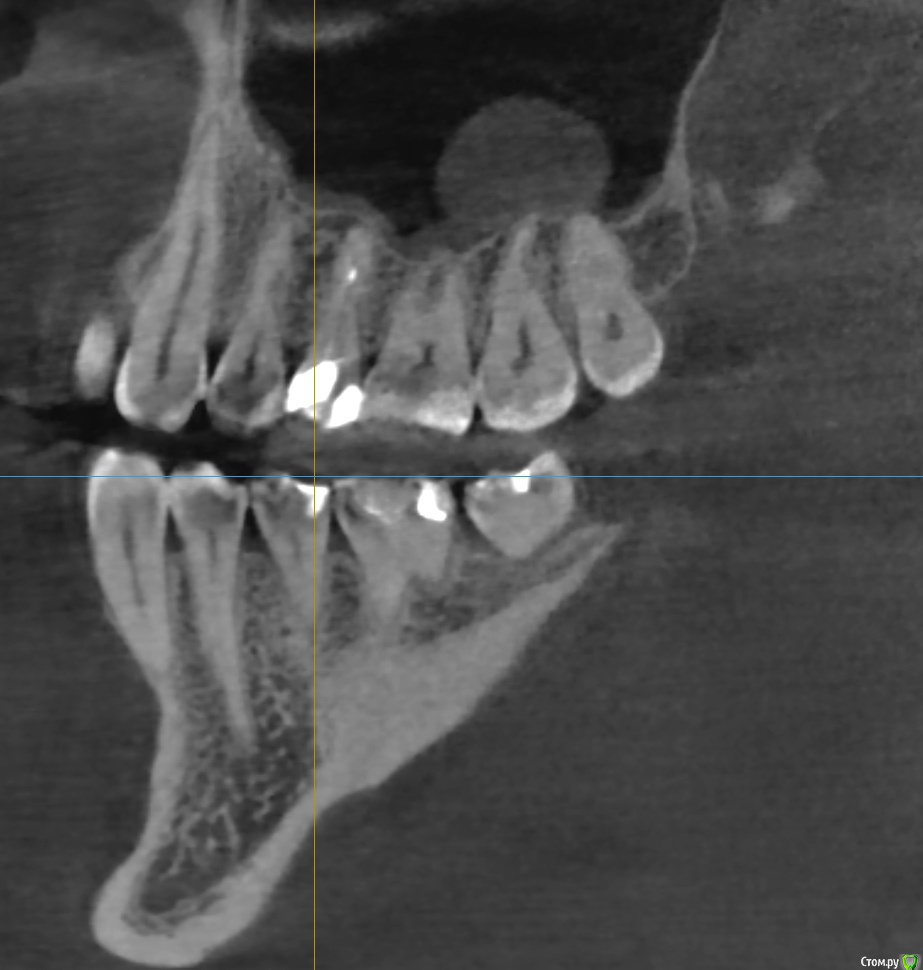

Bier Опубликовано 23 марта, 2018 Поделиться Опубликовано 23 марта, 2018 Если зубы витальные, то подобные образования в лечении не нуждаются. Определите живые ли зубы особенно 7й. Если да, то живите себе спокойно, если нет, то нужно пролечить каналы. У вас есть какая то проблема в области 4-5 зубов, срез КТ стоит нечетко и подробнее не ответить. Ссылка на комментарий

tmporaries Опубликовано 23 марта, 2018 Автор Поделиться Опубликовано 23 марта, 2018 Спасибо за ответы.Киста никак не беспокоит, обнаружили её случайно на КТ.5-ый зуб сверху был перелечен год назад. Ссылка на комментарий